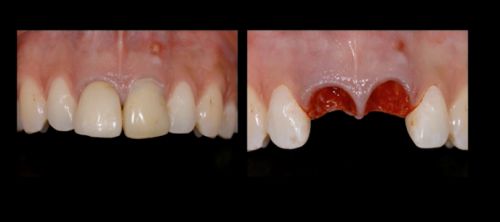

Фото. Удаление 11, 21 зубов из-за большой потери твердых тканей зубов.